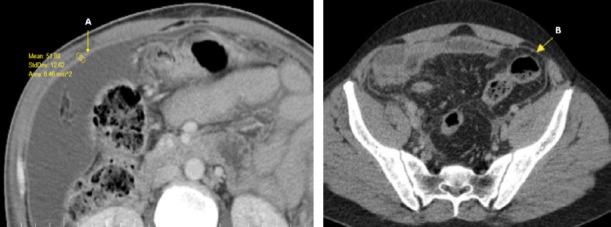

This study included 80 patients, 32 (40%) classified as perforated appendicitis (Group-1) and 48 (60%) as non-perforated appendicitis (Group-2). The C-reactive protein value was found to be statistically higher in Group-1 than in Group-2 (177.5±118.9 and 100.2±87.3 mg / L, respectively; p=0.001). The appendix lumen diameter (p=0.002), appendix wall defect (p<0.001), peritoneal thickening and enhancement (p<0.001), ascites (p=0.031), intra-abdominal abscess (p=0.003), jejunal thickening (p=0.019), ileal thick-ening (p=0.008), and ileus (p=0.035) values were significantly higher in Group-1. In the binominal logistic regression analysis performed with statistically significant data, an appendiceal wall defect (OR: 0.069, 95% CI=0.014-0.327, p=0.001) and peritoneal thickening and enhancement (OR: 0.131, 95% CI=0.024-0.714, p=0.019) were identified as independent variables for perforated appendicitis.

Among CT findings, appendix wall defects and peritoneal thickening and enhancement play an important role in detecting perforation.

本研究包括 80 例患者,32 例(40%)为穿孔性阑尾炎(第 1 组),48 例(60%)为非穿孔性阑尾炎(第 2 组)。第 1 组的 C 反应蛋白值明显高于第 2 组(分别为 177.5±118.9 和 100.2±87.3mg/L;p=0.001)。阑尾腔直径(p=0.002)、阑尾壁缺损(p<0.001)、腹膜增厚和增强(p<0.001)、腹水(p=0.031)、腹腔脓肿(p=0.003)、空肠增厚(p=0.019)、回肠增厚(p=0.008)和肠梗阻(p=0.035)值在第 1 组中明显更高。在进行统计学显著数据的二项逻辑回归分析中,阑尾壁缺损(OR:0.069,95%CI=0.014-0.327,p=0.001)和腹膜增厚和增强(OR:0.131,95%CI=0.024-0.714,p=0.019)被确定为穿孔性阑尾炎的独立变量。

在 CT 发现中,阑尾壁缺损和腹膜增厚和增强在检测穿孔中起着重要作用。